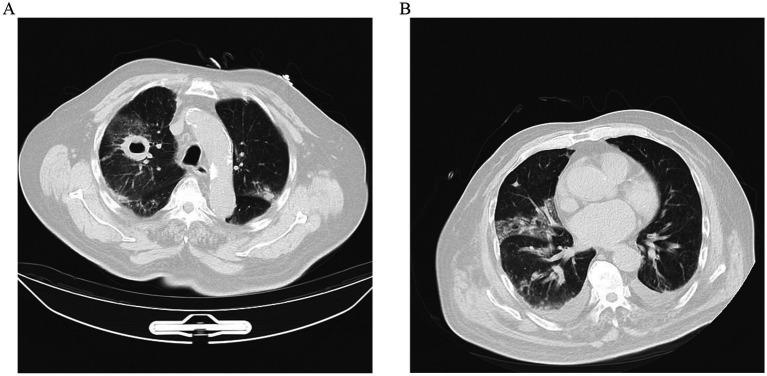

We described a case of 81-year-old man with pulmonary mucormycosis caused by but no other apparent risk factors including diabetes. The diagnosis mainly relied on sputum cultures and clinical manifestations. Despite antifungal therapy, his condition worsened, resulting in mortality.

https://cdn.ncbi.nlm.nih.gov/pmc/blobs/75e4/12014429/1aa1032fa7a4/fmed-12-1544621-g001.jpg